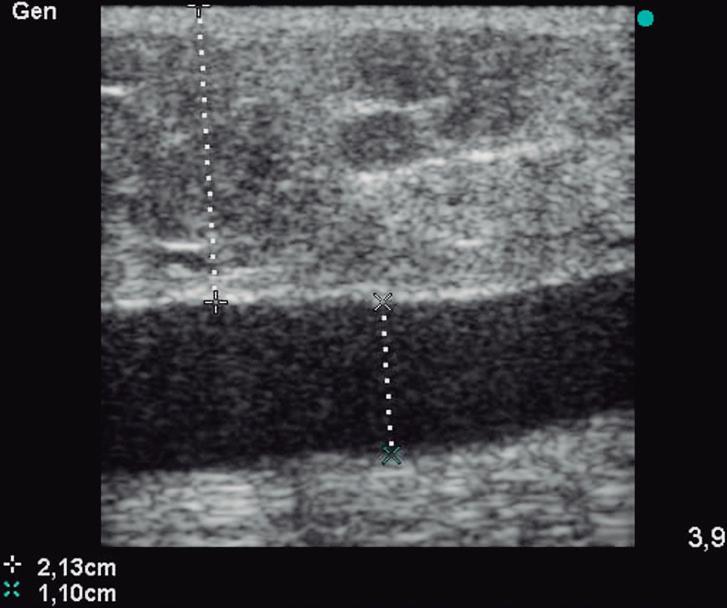

Inicialmente presentó edema y hematoma en la zona, con un área deprimida en la cara externa de muslo. Luego de un mes de evolución, habiéndose reabsorbido el hematoma, se observó una tumoración fluctuante en el sector del traumatismo. El estudio de ecodoppler mostró una colección líquida (hipoecogénica) fusiforme supra aponeurótica, sin flujo arterial ni venoso, con diámetros aproximados de 14 cm x 2 cm x 1,8 cm, diagnosticándose un linfocele postraumático de Morel Lavallée. (Figura 2).

Se inicia tratamiento con drenaje percutáneo eco-guiado con abbocath 14, y se obtienen aproximadamente 40 cc de líquido serohemático. (Figura 3).